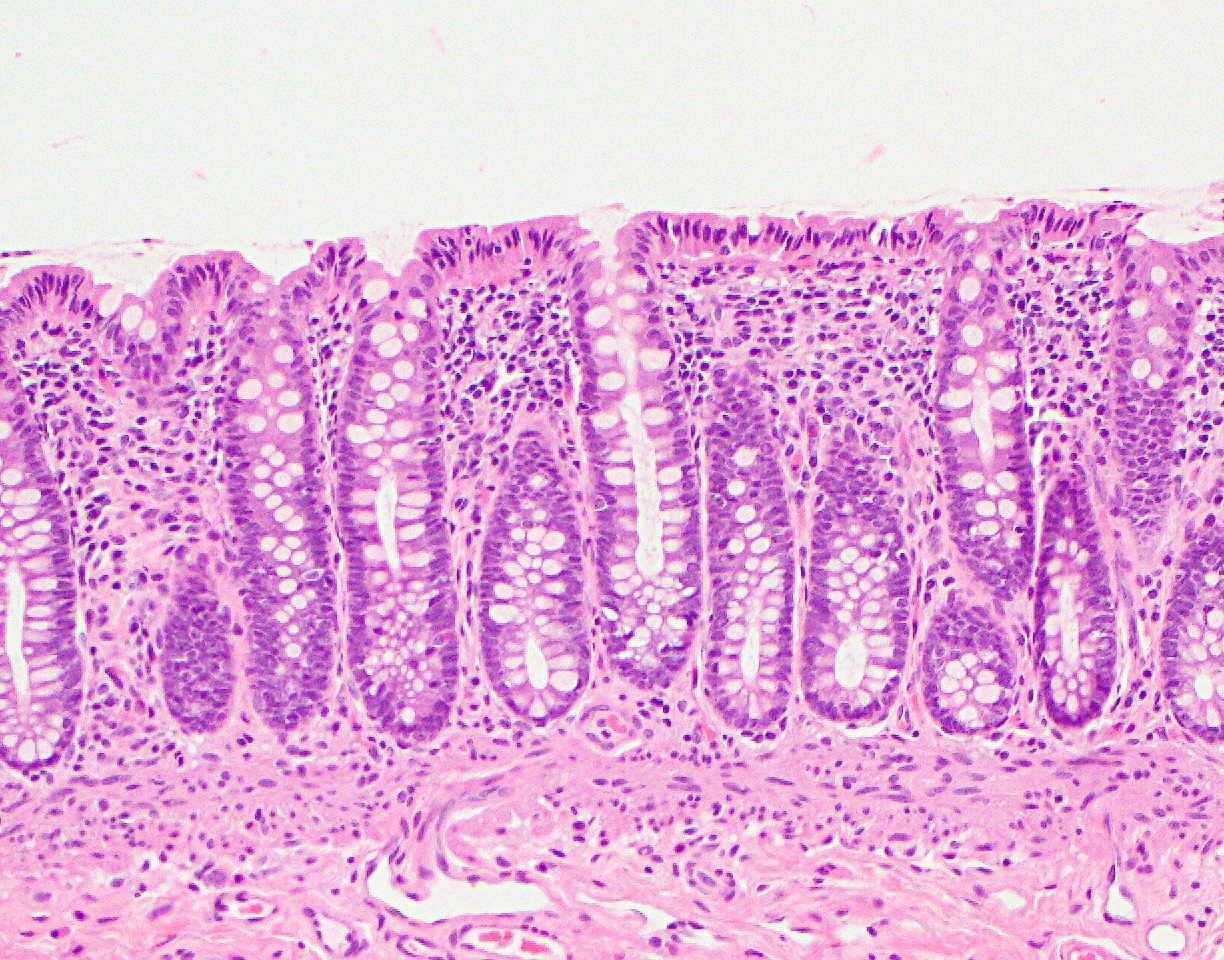

Microscopic (histologic) images

- Epithelium: colonic epithelium is composed of a single layer of the absorptive columnar cells and the goblet cells

- As the epithelium invaginates into the underlying lamina propria, it forms glandular structures called crypts, arranged in a characteristic parallel test tube-like pattern

- Crypt is a functional unit of colon and is primarily lined by the goblet cells

- Absorptive cells: predominant cells in the right colon

- Columnar cells with eosinophilic cytoplasm, basally located nuclei, small apical mucin vacuoles and apical microvilli

- Primarily line the surface epithelium

- Goblet cells: predominant cells in the left colon

- Large cells with intracytoplasmic mucin and basally located hyperchromatic nuclei

- Lamina propria:

- Loose connective tissue rich in capillaries and lymphatics

- Supports the crypts and consists of supportive mesenchymal cells and inflammatory cells

- Architectural discipline of colon with parallel test tube-like arrangement of crypts separated by a consistent amount of lamina propria in between is important to identify